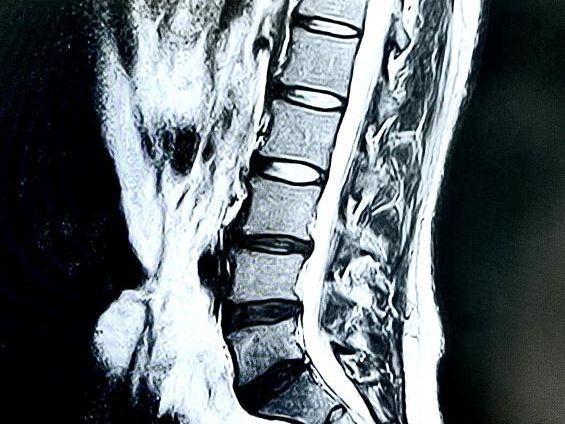

特に無理なことをしていない、無理がかかっていない場合は加齢による腰痛を疑います。レントゲン上で骨と骨の間が狭くなっていることが確認できます。椎間板が狭くなるとそこにある脊椎神経の圧迫がおきて痛みが起きるものを腰椎症といいます。

また椎間板が狭くなり腰椎に影響がある場合は、レントゲン上で徐々に椎間板の上下で白く映るようになります。これは骨棘と呼ばれるもので、放置しておくと腰椎圧迫骨折に進みます。何もしていないのに骨折する「いつの間にか骨折」というものがこれに当たります。

逆に、見た目に明らかに腰が曲がっている、レントゲン上でもはっきりと神経を圧迫しているような腰でも腰痛が全くない人もいらっしゃいます。

ですからレントゲンやMRIで明らかな圧迫があるからといって腰痛があるとは限らないのです。